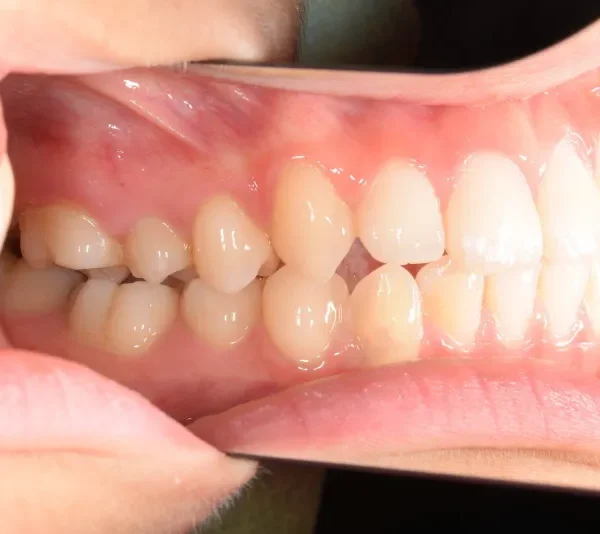

【子供の矯正(一期)】叢生・出っ歯・前歯がゆがんでいる・8才女児【H.M様】

初診時年齢 小学校3年生 (女性) 主訴 出っ歯・前歯がゆがんでいる

診断名 叢生・上顎前突 装置名

状態 永久歯が生える隙間がない(叢生)

ガタガタ・でこぼこに生えている(叢生)

出っ歯(口元が出ている/上顎前突)

出っ歯と前歯のゆがみを主訴に来院されました。

低学年時は取り外しの装置を使用し、高学年になってからは見えにくい固定式の装置を使用して治療しました。